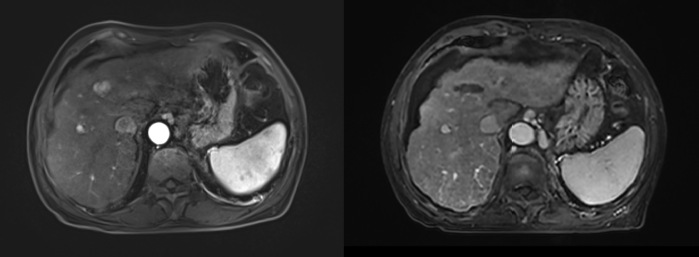

在癌栓与血管通路管理方面,项目提出门静脉癌栓“中山分型”,形成以支架联合内放射治疗为核心的治疗路径,并进一步拓展至门静脉、胆道及肝静脉/下腔静脉等多腔道癌栓的综合介入管理,实现“通路重建—局部控栓—系统协同”的一体化处置。

l 门静脉癌栓的介入治疗